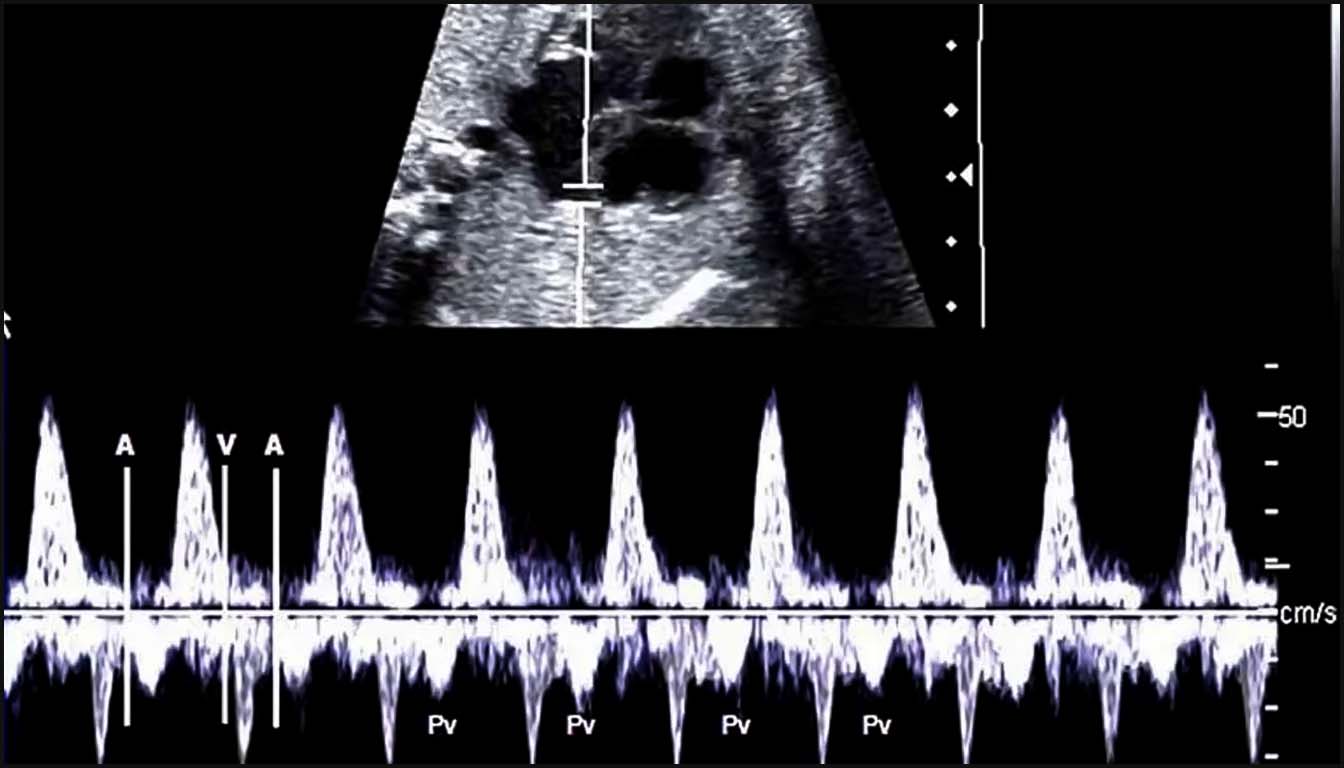

1. Le canal d’Arantius (DV) : L’évaluation par Doppler pulsé du flux veineux est un indicateur puissant de la fonction cardiaque droite. Un flux anormal, caractérisé par une onde ‘a’ inversée ou absente lors de la contraction auriculaire, est associé à un risque accru de CC structurelles, d’aneuploïdies et d’issue de grossesse défavorable. Chez les fœtus euploïdes présentant une CN augmentée, une onde ‘a’ anormale porte la prévalence des malformations cardiaques majeures à environ 15-20 %.

2. La régurgitation tricuspide (TR) : La présence d’un flux rétrograde à travers la valve tricuspide pendant la systole ventriculaire est un signe d’appel majeur. Pour être cliniquement significative au premier trimestre, la TR doit être visible sur au moins la moitié de la systole avec une vélocité supérieure à 60 cm/s. La combinaison d’une CN augmentée, d’une TR et d’un flux anormal dans le DV permet d’identifier jusqu’à 55,5 % des fœtus porteurs d’une CC majeure avec un taux de faux positifs de seulement 8,8 %.

• Arythmies : Le Doppler simultané de la veine cave supérieure et de l’aorte permet de documenter la relation entre les contractions auriculaires et ventriculaires, facilitant le diagnostic précis des tachycardies (ex: flutter auriculaire) ou des blocs auriculoventriculaires.

1. Analyse de la fonction diastolique et pressions veineuses

La fonction diastolique fœtale est principalement évaluée par le Doppler pulsé au niveau des valves auriculo-ventriculaires (mitrale et tricuspide). Normalement, le flux présente un aspect biphasique avec une onde E (remplissage passif) et une onde A (contraction auriculaire). Une inversion du rapport E/A ou un flux monophasique sont des signes de réduction de la compliance ventriculaire ou d’augmentation des pressions de remplissage.

Le Doppler veineux est le reflet direct des pressions dans l’oreillette droite. L’analyse du canal d’Arantius (DV) est ici cruciale : un flux antégrade est normal, tandis qu’une onde ‘a’ absente ou inversée indique une augmentation de la pression veineuse centrale et une dysfonction cardiaque droite. Si la situation s’aggrave, ces anomalies de pression se transmettent à la veine ombilicale, où l’on observe alors des pulsations anormales, signe pré-terminal de défaillance cardiaque.

1. Évaluation du rythme et de la conduction

Le Doppler est l’outil de référence pour diagnostiquer les arythmies fœtales en l’absence d’ECG direct. Le Doppler pulsé simultané de la veine cave supérieure et de l’aorte permet de documenter la relation temporelle entre les événements auriculaires (onde ‘a’ de la veine) et ventriculaires (flux aortique). Cette technique permet de différencier :

1. Les tachycardies supraventriculaires (SVT) par réentrée (conduction 1:1).

2. Le flutter auriculaire, caractérisé par une fréquence auriculaire très élevée (jusqu’à 400 bpm) avec un bloc auriculo-ventriculaire variable.

3. Le bloc auriculo-ventriculaire (BAV) complet, où l’on observe une dissociation totale entre les contractions auriculaires et ventriculaires, souvent associé à des maladies auto-immunes maternelles.

Le diagnostic repose initialement sur l’échographie fœtale, qui utilise le mode M et le Doppler pulsé pour analyser la relation temporelle entre les contractions auriculaires et ventriculaires. Les techniques de Doppler simultané (Veine cave supérieure/Aorte ou Influx mitral/Efflux aortique) sont indispensables pour définir le mécanisme de l’arythmie, en mesurant l’intervalle mécanique PR (conduction AV).